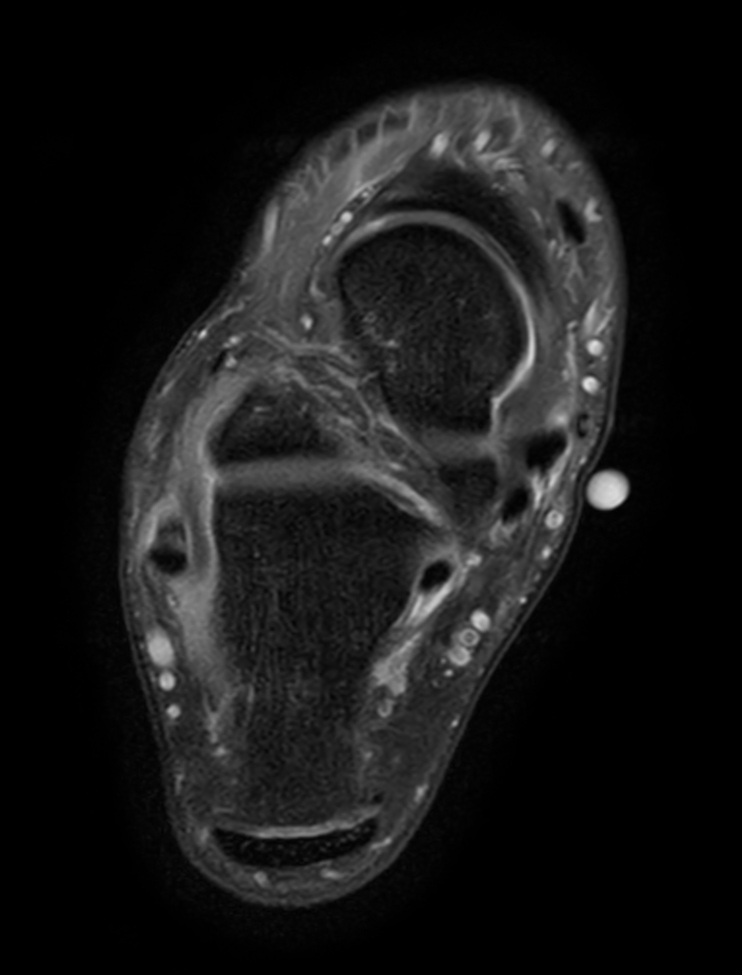

Axial T1w TSE